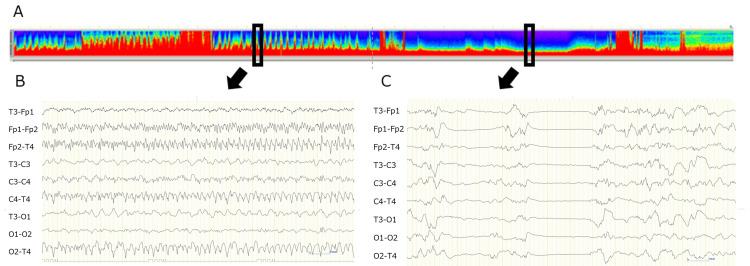

Febrile infection-related epilepsy syndrome (FIRES) is a type of new-onset refractory status epilepticus (NORSE) that occurs in previously healthy children. Conventional antiepileptic drugs (AEDs) often fail to control seizures, necessitating the use of high-dose anesthetics, which can lead to severe complications and poor outcomes. Perampanel has shown promise in the treatment of refractory epilepsy; however, its role in FIRES remains underexplored. We report the case of a 13-year-old boy with FIRES, which was characterized by refractory status epilepticus following a febrile illness. Although some AEDs were administered, high-dose thiopental and ventilator support were required. Perampanel at a starting dose of 2 mg/day and titrated to 8 mg/day enabled successful weaning from thiopental and extubation. The patient eventually became seizure-free on clobazam and levetiracetam. On follow-up, the patient exhibited memory and behavioral issues, along with bilateral hippocampal atrophy on MRI. This case demonstrated the potential role of perampanel in managing FIRES by reducing the need for prolonged barbiturate use and ventilator dependence. Although there was persistent cognitive impairment, which was likely secondary to hippocampal damage, perampanel showed a favorable safety profile. This case suggested that perampanel is a valuable addition to FIRES treatment. Further studies are required to confirm its efficacy.

发热感染相关性癫痫综合征(FIRES)是一种新发难治性癫痫持续状态(NORSE),发生于既往健康的儿童。传统抗癫痫药物(AEDs)往往无法控制癫痫发作,因此需要使用高剂量麻醉剂,这可能导致严重并发症和不良预后。吡仑帕奈在难治性癫痫治疗中已显示出前景;然而,其在FIRES中的作用仍未得到充分探索。我们报告了一例13岁患有FIRES的男孩病例,其特征为发热性疾病后出现难治性癫痫持续状态。尽管使用了一些AEDs,但仍需要高剂量硫喷妥钠和呼吸机支持。起始剂量为2mg/天的吡仑帕奈,并滴定至8mg/天,使患者成功停用硫喷妥钠并拔管。患者最终在服用氯巴占和左乙拉西坦后无癫痫发作。随访时,患者出现记忆和行为问题,MRI显示双侧海马萎缩。该病例证明了吡仑帕奈在管理FIRES方面的潜在作用,即减少长期使用巴比妥类药物的需求和对呼吸机的依赖。尽管存在持续性认知障碍,这可能继发于海马损伤,但吡仑帕奈显示出良好的安全性。该病例表明吡仑帕奈是FIRES治疗中有价值的补充药物。需要进一步研究来证实其疗效。